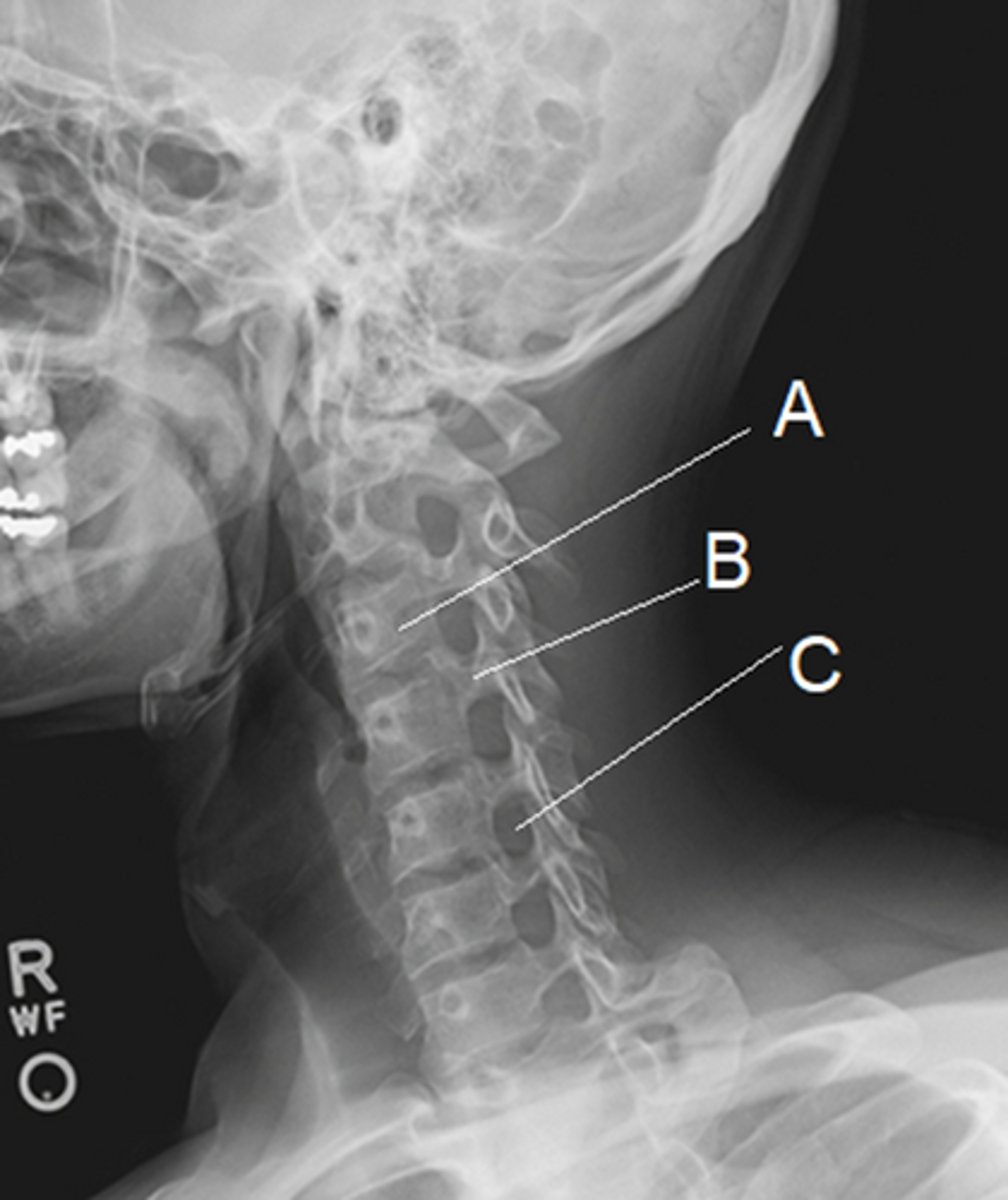

In the image, '1' represents the:

Lamina

In the image, 'B' represents:

Zygapopgyseal joint

In the image, 'C' represents:

Intervertebral foramen (C5-6)